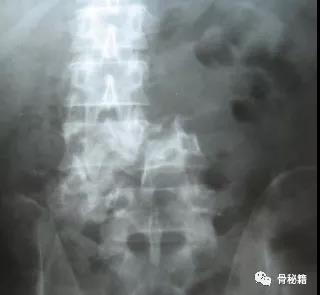

单纯的压缩骨折

对于单纯的压缩骨折来说,应用AO经典的撑开复位技术就可以达到复位